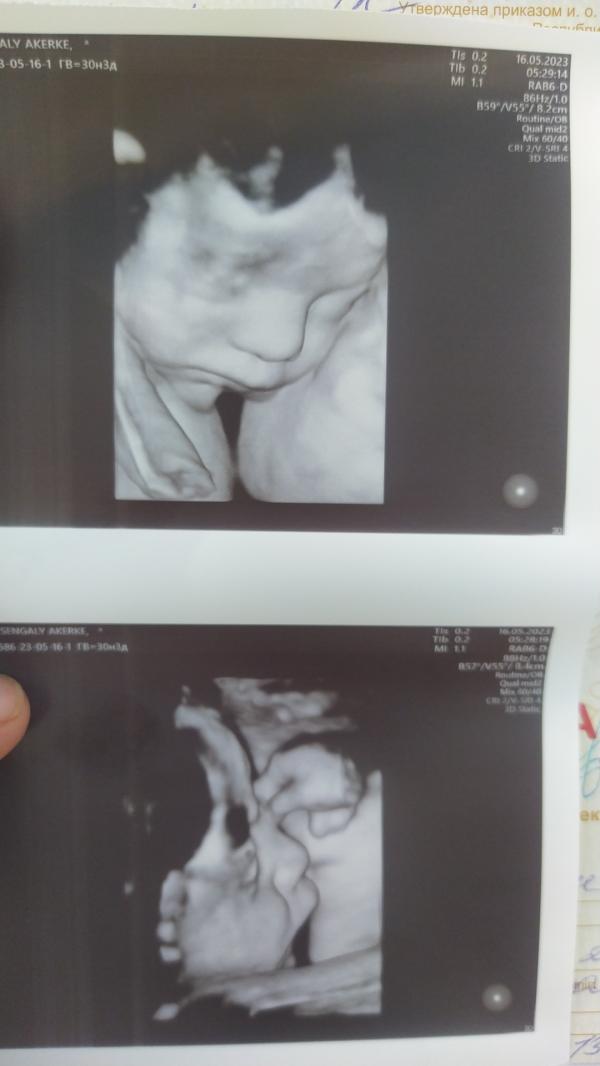

Сегодня прошла 3 скрининг 😍 На сына похож что ли малыш♥️